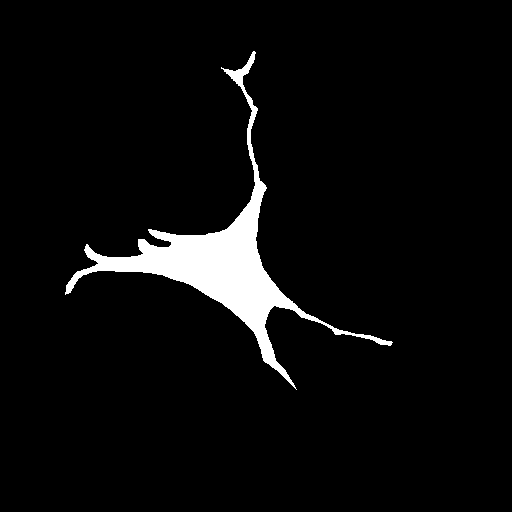

We evaluate the performance of each approach with five classical metrics: intersection over union (IoU), Dice score, precision, recall, and Hausdorff Distance (HD). We provide results on datasets , , and in Tables 1, 2, and 3, respectively. In Figure 2, we also illustrate representative segmentation results on dataset for each methods.

GT

The original U-net model produces poor segmentation results on datasets and while performing better on dataset . CE-net performs better than U-net and results in a strong recall in all three datasets. Attention U-net outperforms both CE-net and U-net on most metrics. The Attention gates incorporated in AURA-net allow outperforming CE-net, while its pre-trained layers help improve over Attention U-net. On top of that, the AC loss provides the network with additional information on object regions. As a result, AURA-net generally outperforms competing approaches. It occasionally scores closely to Attention U-net and CE-net, and even concedes a lead on recall in datasets and and on precision in dataset . It however performs best overall, with a consistent clear advantage on the IoU, Dice, and HD metrics.

Raw

GT

AURA-net

In Figure 3, we illustrate failure cases in dataset . In the first example, AURA-net fails to correctly segment the bottom part of the object. This outcome is unsurprising considering that the raw image exhibits a lower SNR than any of the training data. In the second example, the segmentation mask predicted by AURA-net contains several objects, yielding a poor overlap with the ground truth annotation featuring a single cell. However, the original image reveals the presence of a second, partially cropped non-annotated cell. In this case, part of AURA-net’s “false” detection are actually correct predictions that have been omitted in ground truth annotations.